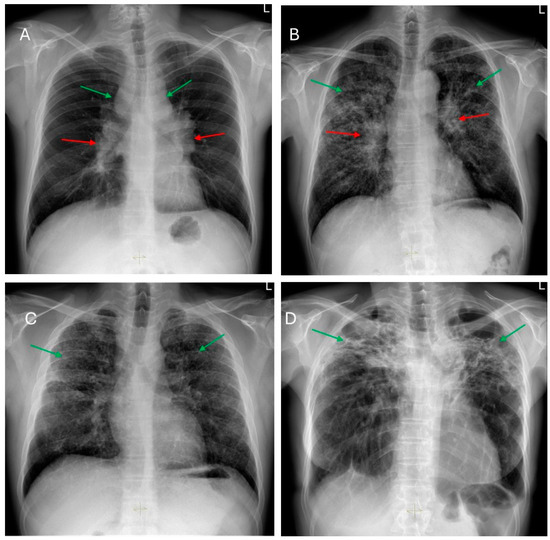

Presence and Evolution of Radiological Changes at 6 and 12 Months After COVID-19 Pneumonia and Their Risk Factors

Background and Objectives: The pulmonary sequelae of COVID-19 and their evolution are of interest to the scientific community. We aimed to determine the radiological changes at 6 and 12 months after COVID-19 pneumonia, its evolution and its risk factors. Materials and Methods: This retrospective longitudinal study included adults admitted for COVID-19 pneumonia from 1 March 2020 to 30 April 2021 who had a high-resolution computed tomography (HRCT) scan at 6 months and 12 months after hospital discharge. The primary outcome was the appearance of radiological abnormalities on HRCT and the number of lung segments affected by them at 6 and 12 months, while the main explanatory variables were about the disease course, analytical parameters and treatment. Results: This study included n = 108 patients, with a mean age of 64 years. There was a decrease in the percentage of patients presenting parenchymal (93.5% to 88.9%, p < 0.001) and reticular (63% to 62%, p < 0.001) patterns on HRCT at 12 months compared to 6, and an increase in those presenting a fibrotic pattern (62% to 63.9%, p < 0.001). Ground-glass opacities were the most frequent radiological change at 6 and 12 months (91.7% and 87%, respectively). There was a significant reduction in the total number of lung segments with ground-glass opacities (445 to 382, p < 0.001) and consolidation (158 to 136, p = 0.019) and an increase in those with bronchiectasis (66 to 80, p = 0.033) between the two moments. After multivariate analysis, high-flow oxygen therapy (HFOT), highest ferritin levels, hypertension and ≥71 years showed an association with the development of subpleural parenchymal bands, consolidation, bronchiectasis and septal thickening at 6 and 12 months. Conclusions: Parenchymal patterns seem to be more frequent than reticular and fibrotic patterns after COVID-19 pneumonia. The fibrotic pattern was the only one that worsened significantly over time, with bronchiectasis being the only change that increased at 12 months. Older age, hypertension, the need for HFOT, and high levels of ferritin may be directly associated with worse radiological outcomes after COVID-19 pneumonia. Full article